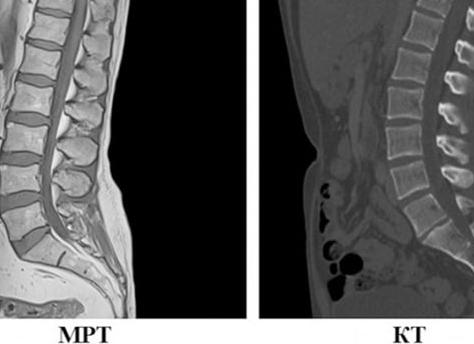

Компьютерная томография подразумевает использование рентгеновских лучей. Они пронизывают исследуемую область тела, а полученные данные обрабатывает специальный мощный компьютер. В отличие от обычного рентгена, томограф имеет несколько датчиков-излучателей, что позволяет делать снимки в двух или более плоскостях. Таким образом получают объемную картинку обследуемых органов. Само обследование посредством КТ длится около минуты (время зависит от типа устройства).

Принцип работы МРТ-диагностики сводится к воздействию сильного магнитного поля на организм человека. Оно заставляет протоны атомов водорода в человеческом теле подавать слабый радиосигнал, который и улавливается мощными встроенными датчиками. Информация поступает в специальный компьютер, а тот в свою очередь делает подробную 3D-модель исследуемой области организма. Иногда МРТ используют как вспомогательную процедуру прямо во время хирургической операции, ведь устройство томографа позволяет наблюдать процессы, протекающие внутри организма, в режиме «реального времени». Стандартное исследование с помощью МРТ происходит в течение 30-40 минут. Перед процедурой пациент снимает все металлические предметы, во избежание их взаимодействия с магнитным полем. Томограф выполняет несколько последовательных снимков, между которыми есть небольшие паузы – в это время пациент может немного пошевелиться (но движение в районе исследуемой области исключено).

Точность аппаратной диагностики определяется целесообразностью применения того или иного метода. МРТ актуальна в тех случаях, когда нужно исследовать мягкие ткани, нервную систему, мышцы, суставы и т.д. Но костная система визуализируются с меньшей четкостью по сравнению с КТ, ведь ткани скелета содержат лишь небольшое количество протонов водорода.

Поэтому при заболеваниях, связанных с опухолями, головным и спинным мозгом, связками, мышцами, суставами врач, скорее всего, назначит вам МРТ. А когда дело касается диагностики патологий костей черепа, зубов, сосудов, грудной клетки (например, туберкулез и пневмония), щитовидной железы и позвоночника – то предпочтительным способом станет компьютерная томография.

Строго говоря, КТ отличается тем, что позволяет рассмотреть физическое состояние рассматриваемых объектов, а МРТ служит для выявления их химических характеристик. Поэтому, хотя оба метода могут использоваться параллельно для более точного обследования одного и того же органа, КТ чаще применяется для сканирования костных, а МРТ – мягких тканей.